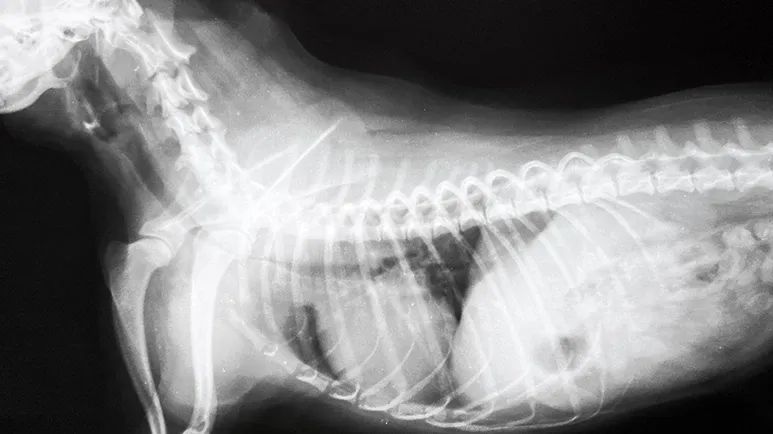

Tracheal collapse can sometimes be seen on a standard X-ray as a narrowing of the tracheal lumen. Fluoroscopy, which is a moving X-ray, allows your veterinarian to watch your dog's trachea as he breathes in and out.